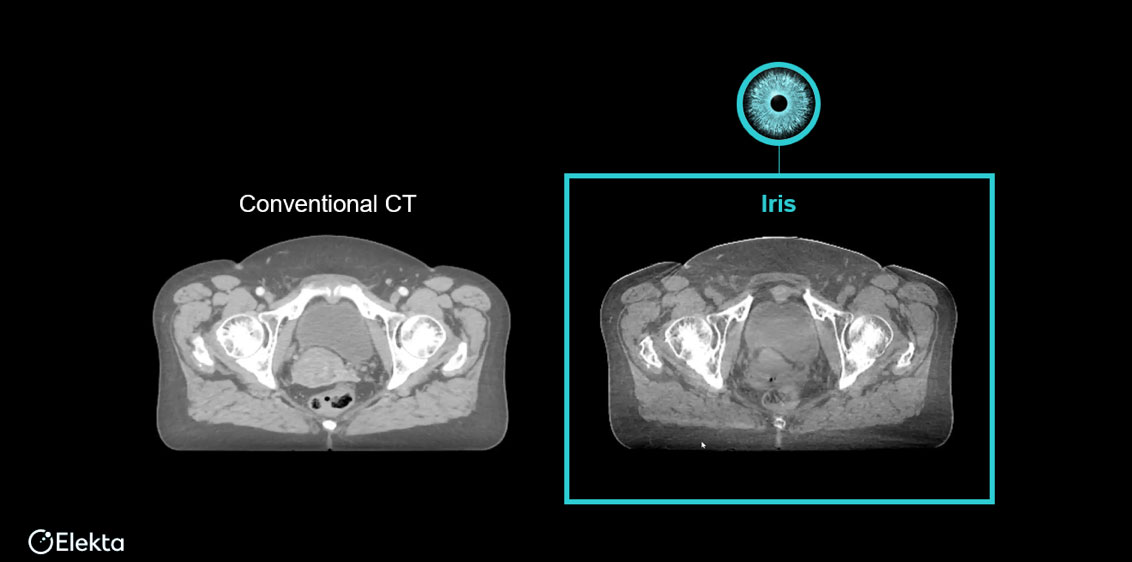

消除影像干扰信号,保留真实组织细节——机载影像的技术创新突破

Iris® 高清AI增强影像通过全新解剖特异性AI散射校正与PolyQuant CT重建算法,从根源攻克传统CBCT散射干扰、软组织对比度不足等痛点。结合GPU加速计算,实现极速迭代影像"秒级"重建,呈现病灶与周围正常组织的清晰细微结构,助力精准放疗技术的临床应用与突破。

Iris® 高清晰CBCT影像与CT影像